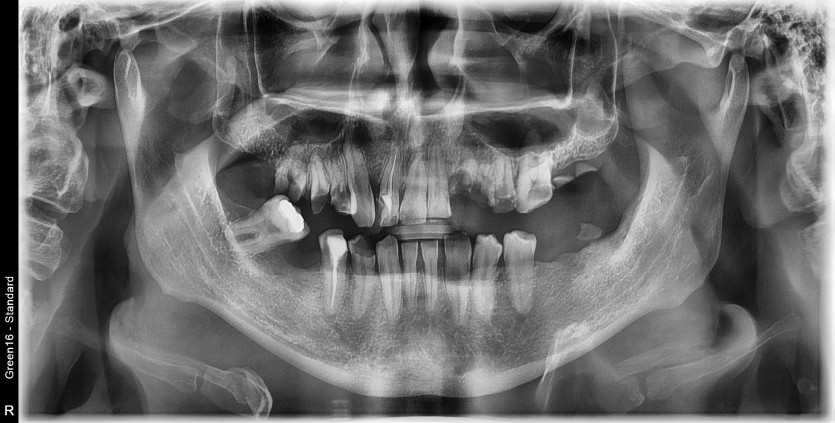

만 36세 전체 임플란트 증례

전체 임플란트 증례입니다.

18개의 임플란트로 완성하였습니다.